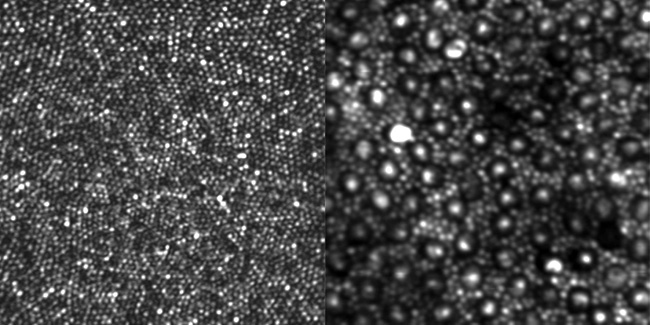

ADAPTIVE OPTICS/OPHTHALMOLOGY Firstever clear, direct imaging of rod